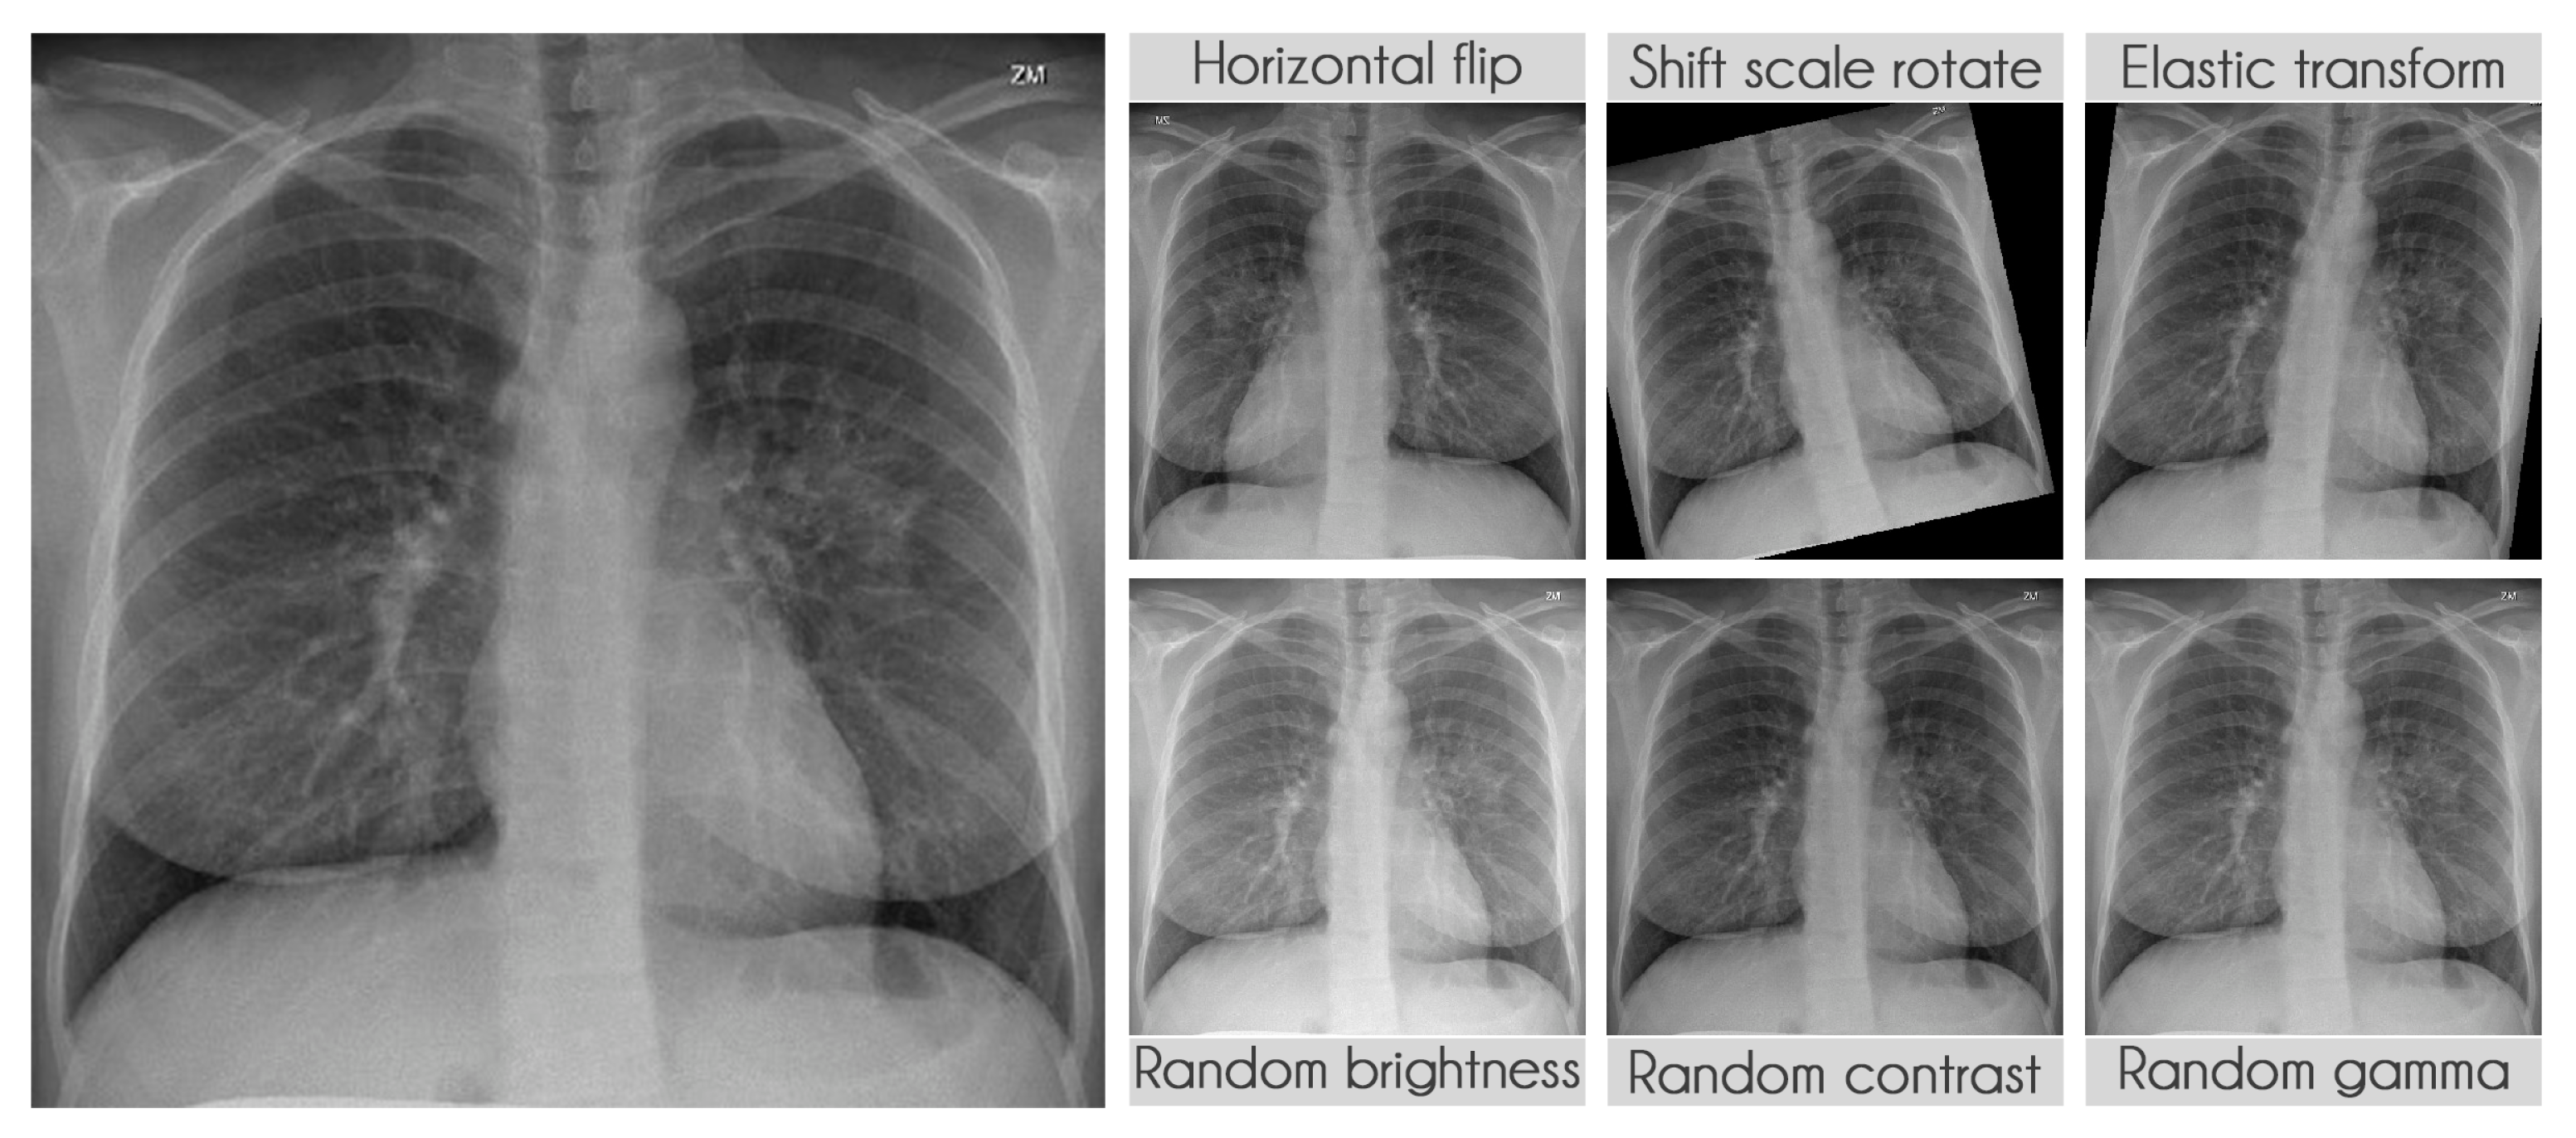

3.2.4. Data Augmentation

Table 9 presents the transformations used during training along with their parameters. The probability of applying each transformation was kept at the default value of 50%. We used the library albumentations to perform all transformations [

Figure 6 displays some examples of the transformations applied.